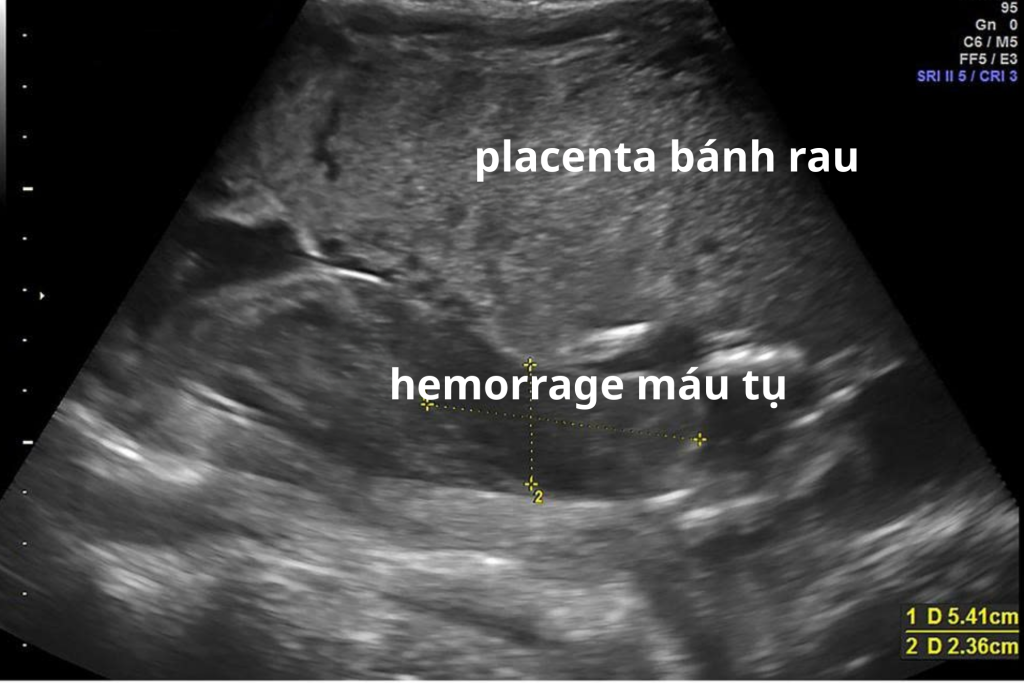

- Máu có thể tụ phía sau bánh nhau

Nghi ngờ nhau bong non trên siêu âm có chắc chắn không?

Siêu âm có thể hỗ trợ phát hiện khối máu tụ sau bánh nhau. Tuy nhiên:

- Không phải mọi trường hợp đều nhìn thấy rõ trên siêu âm

- Giai đoạn sớm có thể chưa có hình ảnh đặc hiệu

- Siêu âm bình thường không loại trừ hoàn toàn nhau bong non

Vì vậy, khi tìm hiểu dấu hiệu nhau bong non là gì, cần hiểu rằng triệu chứng lâm sàng quan trọng hơn hình ảnh siêu âm trong nhiều trường hợp.